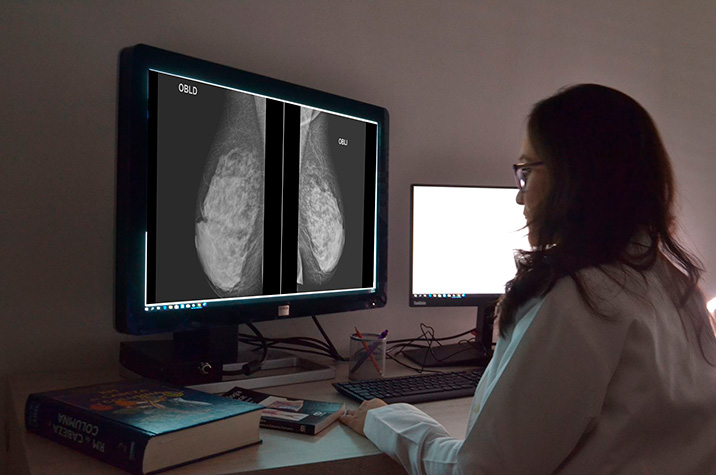

Detección del cáncer de mama mediante mamografía, tomosíntesis mamaria digital y resonancia magnética según la densidad mamaria

28 agosto 2024

En este análisis de efectividad comparativa basado en modelos, la resonancia magnética suplementaria para mujeres con mamas densas sumada al cribado con mamografía condujo a mayores beneficios y también mayores daños. El balance de esta compensación para el uso de RMN suplementaria fue más favorable cuando se dirigió a mujeres con mamas extremadamente densas que comprenden aproximadamente el 10% de la población. JAMA Internal Medicine, 26 de agosto de 2024.